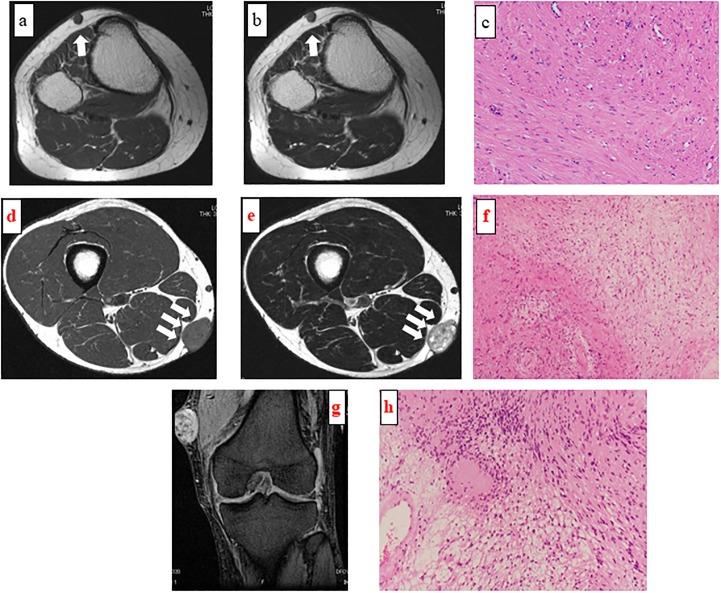

Many surgeons participate in the management of superficial soft tissue masses, and a preoperative incorrect diagnosis frequently results in dismal oncological outcomes. The aim of this study was to identify distinguishing magnetic resonance imaging features between malignant and non-malignant lesions.

The clinicopathological data for 219 patients (men 114; women 105) with superficial soft tissue masses treated from January 2007 to December 2016 in our institution were retrospectively analyzed. The median age at the first visit was 55.6 years (range 1-90 years). MRI findings of tumor size, margin, lobulation, intratumoral hemorrhage, peritumoral edema, and tumor-fascia relationship were compared with the final histological diagnosis and tumor grade.

Univariate analysis revealed significant relationships between histologically malignant lesions and tumor size ≥5 cm (p = 0.035), positive peritumoral edema (p = 0.031), and tumor-fascia relationship (p<0.001), but not margin (p = 0.107), lobulation (p = 0.071), and intratumoral hemorrhage (p = 0.17). In addition, using multivariate analysis, the tumor-fascia relationship (p<0.001) and tumor size were significant factors. A significant correlation between tumor-fascia relationship and malignancy (p<0.001) was observed; such a relationship was, however, not observed for tumor grade (p = 0.43).

Tumors measuring ≥5 cm and the tumor-fascia relationship on magnetic resonance imaging are highly indicative of malignancy. When superficial soft tissue masses cross the superficial fascia and form obtuse angles with the fascia, sarcoma should be considered. The tumor-fascia relationship can offer surgeons useful information regarding the status of superficial soft tissue masses.